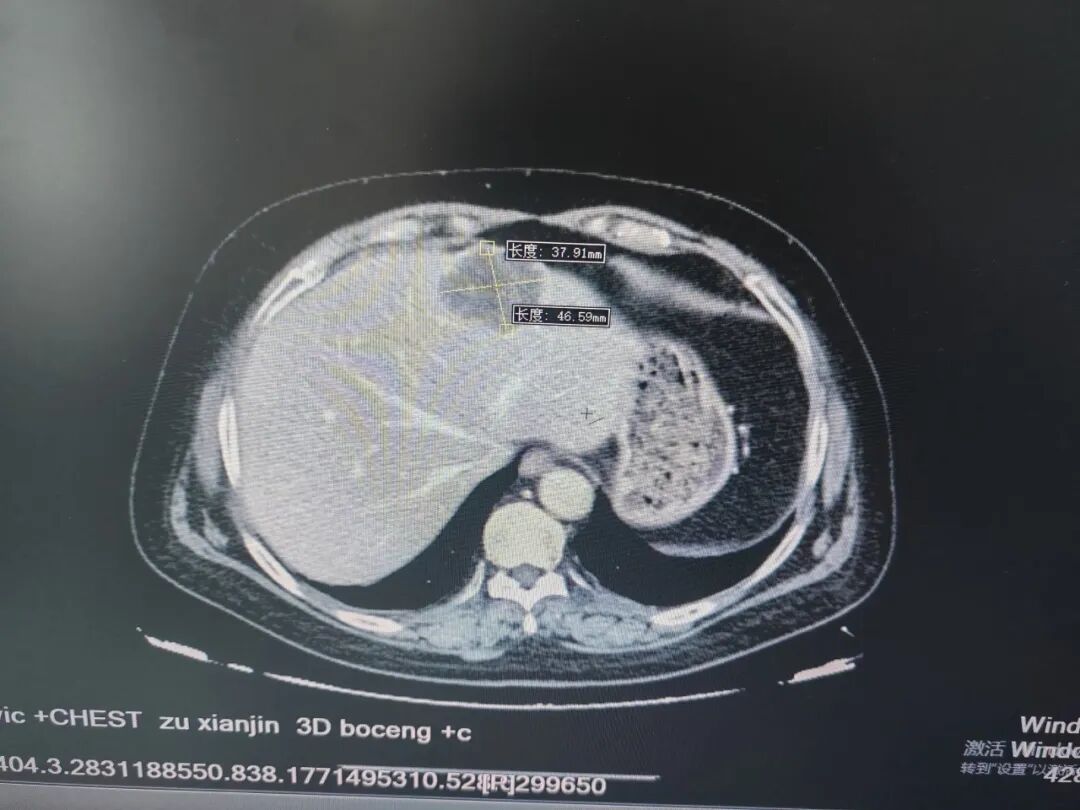

▲肝脏CT增强下显示的肿块

肝脏CT增强显示:肝S2段占位性病变。

首先在脐与耻骨联合中点处做1厘米弧形切口,腹腔镜下,探查肝脏表面可见左肝外叶有一4×5厘米肿块——这是一个差不多有鸡蛋那么大的东西。